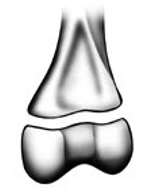

Grade the Salter-Harris fracture?

1 - straight through the physis

Straight across